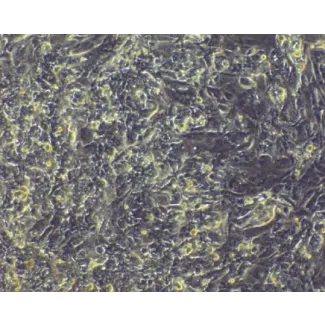

ScienCell addresses this by offering HPSC-derived Cardiomyocytes (H9-CM, Cat. No. 6250), which provides an alternative supply of cardiomyocytes for various studies. These cells are differentiated from pluripotent stem cell line (H9). They are developed under serum-free and feeder-free conditions at high efficiency, then enriched for contracting cells.

HPSC-derived Cardiomyocytes (Catalog No. 6250)